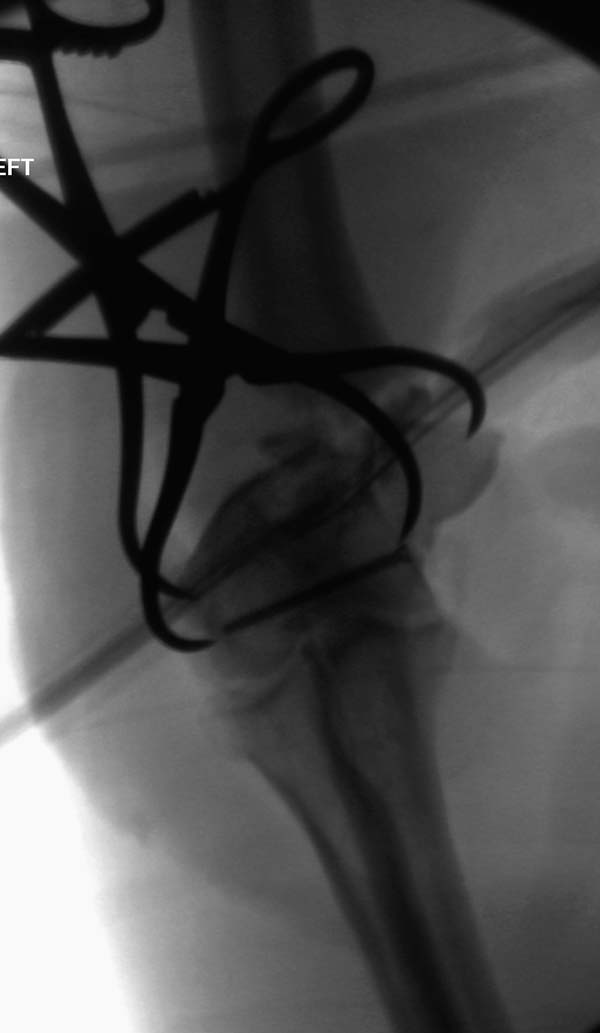

Примеры: первому более 15 лет фиксирован шурупом и tension band

technique, а второй перелом открытый больной 80 лет, после наружного

фиксатора в первом этапе и окончательная фиксация вторично. Третьий раз

внесуставная остеотомия...

Вложение не в текстовом формате было извлечено&hellip;

Имя     : 2-2 Distal Humerus.jpg

Тип     : image/jpeg

Размер  : 43412 байтов

Описание: отсутствует

Url     : http://weborto.net:8080/pipermail/ortho/attachments/20130604/c45a379f/attachment-0021.jpg